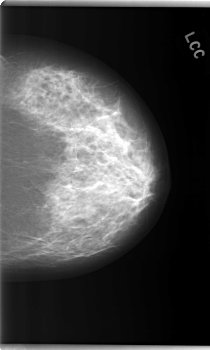

C_0243_1.LEFT_CC

LEFT_CC LINES 5944 PIXELS_PER_LINE 3568 BITS_PER_PIXEL 12 RESOLUTION 50 NON_OVERLAY